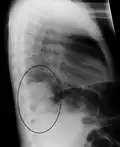

Normal lateral CXR -

Right lower lobe pneumonia as seen on a lateral CXR